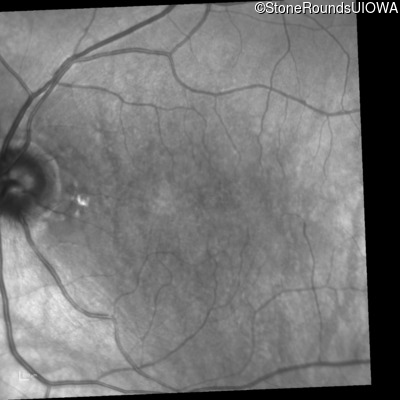

Occult Macular Dystrophy (IIE)

Age at visit:

56 years

OD

OS

20/200 sc

10/160 -1 sc

Occult Macular Dystrophy

RP1L1

Arg45Trp CGG>TGG

AD